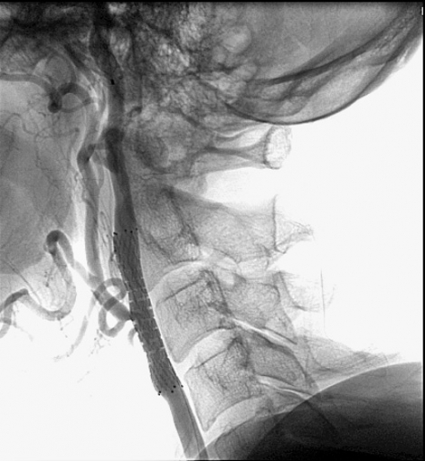

Att behandla stenos i arteria carotis interna i strokeförebyggande syfte kan göras antingen genom öppen operation (karotisendarterektomi) eller med endovaskulär teknik (stentning). Båda metoderna kan tillämpas som primär- och sekundärprofylax på asymtomatiska respektive symtomatiska patienter.

Stentbehandling har blivit ett tilltalande, och i vissa länder ofta tillämpat, alternativ till öppen operation – främst på grund av dess minimalinvasiva natur.